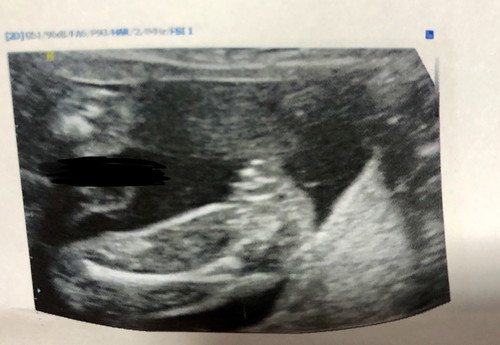

เพศลูก

หมอบอกผู้หญิง 99% คุณแม่ท่านอื่นว่าอย่างไรบ้างคะ เราไม่ค่อยมั่นใจค่ะ ช่วยดูหน่อยนะคะขอบคุณค่ะ

ส่วนใหญ่ในใบซาวน์หรือหมอบอกจะตรงค่ะ